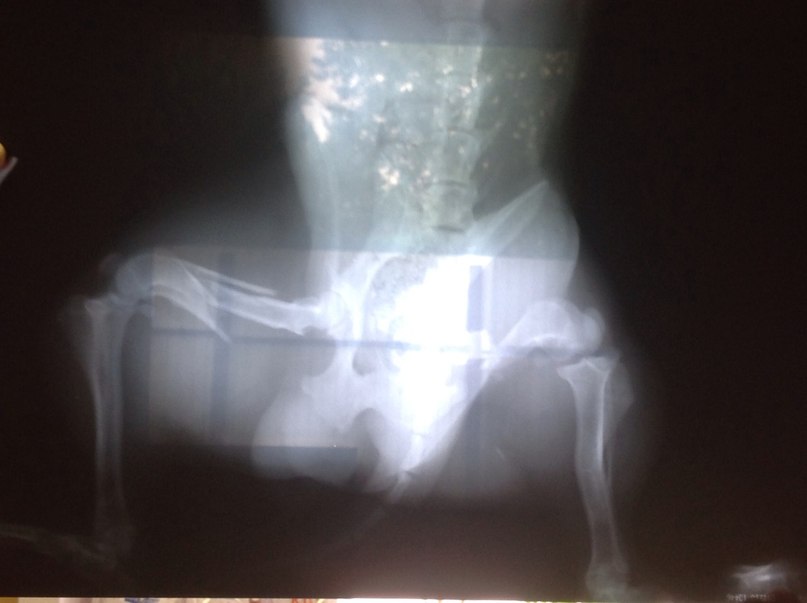

улица Красноярская, сбитый пес! перелом со смещением тазовых костей с обеих сторон! Цена операции около 4000 т.р.

13:53 Открытьулица Красноярская, сбитый пес! перелом со смещением тазовых костей с обеих сторон! Цена операции около 4000 т.р.

На прошлой неделе, по улице Красноярская машина переехала колесом маленького пса..